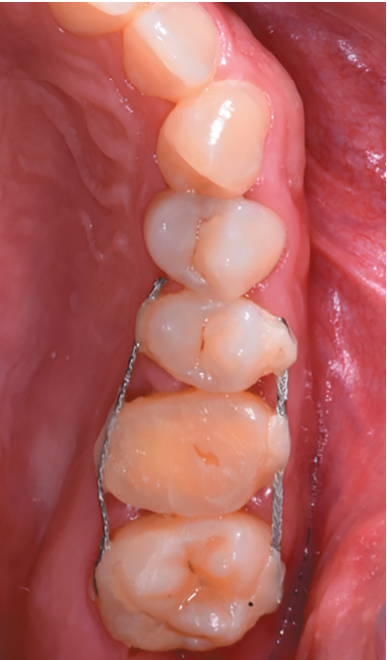

The 2.5, 2.6 and 2.7 teeth were then prepared by etching with orthophosphoric acid at 37% (3M Scotchbond UniversalTM, Minnesota, USA) for 20 seconds (Figure 11). After heavy washing of the etched surface with water, self-etch adhesive (3M Scotchbond UniversalTM, Minnesota, USA) was applied to fix the rigid wire with fluid composite resin (CharismaTM, Kulzer, Hanau, Germany) and conventional composite resin (G-aenialTM, GC, Leuven, Belgium) (Figure 12).

After reducing the occlusion, a cross stitch with monofilament suture (AragoTM, Barcelona, Spain) was applied around the transplanted tooth to increase its fixation (Figure 13), performing an intraoperative periapical radiograph with parallelism technique (Figure 14).